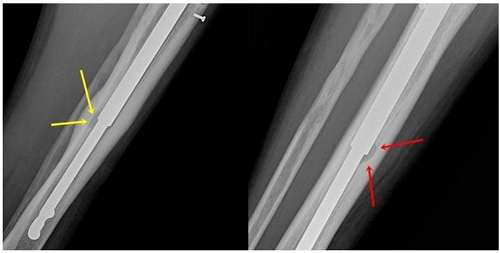

<½ºÆ®¶óÀ̵å ȯÀÚÀÇ »À°¡ ³ìÀº °ÍÀÌ È®ÀεǴ X-RAY / »çÁøÁ¦°ø=´ºº»Á¤Çü¿Ü°ú>

<½ºÅ©·ù±¸¸ÛÀÇ 8~10¹è¿¡ ´ÞÇÏ´Â °ñ¿ëÇØ Çö»ó / »çÁøÁ¦°ø=´ºº»Á¤Çü¿Ü°ú>

½ÇÁ¦ ȯÀÚ »ç·Ê

ÇÊÀÚ´Â »çÀü¿¹¾àÀ» ÅëÇØ Stride ¼ö¼úÀ» ¹ÞÀº ÈÄ °ñ¿ëÇØ Áõ»óÀÌ ¹ß»ýÇÑ Å¸ º´¿ø ȯÀÚµéÀ» Á÷Á¢ Áø´ÜÇÑ °æÇèÀÌ ÀÖ´Ù. ÁýµµÇÑ º´¿ø¿¡¼­´Â X-RAY¸¦ ÃÔ¿µÇßÀ½¿¡µµ ¿øÀΰú Áõ»óÀ» ¸íÈ®È÷ Àü´Þ¹ÞÁö ¸øÇß°í, ÇÊÀÚ¸¦ ÅëÇØ óÀ½À¸·Î °ñ¿ëÇØ Áø´ÜÀ» ¹Þ¾Ò´Ù´Â ȯÀڵ鵵 ÀÖ¾ú´Ù. ½ºÆ®¶óÀ̵忡 °ü½ÉÀÌ ¾ø¾ú´ø ³ª´Â ȯÀÚÀÇ »óŸ¦ º¸°í ºÎ·ªºÎ·ª ÇØ´ç ³í¹®µéÀ» °Ë»öÇØ º¸±âµµ Çß´Ù. ½ÇÁ¦ ȯÀÚ ¿µ»ó¿¡¼­´Â ³»°íÁ¤ ½ºÅ©·ù ±¸¸Ûº¸´Ù 8~10¹è °¡·® »À°¡ ¼Õ»óµÈ »ç·Ê°¡ È®ÀεǾú´Ù. ´ÙÇàÈ÷ ÀåÄ¡¸¦ ½Å¼ÓÈ÷ Á¦°ÅÇÏ°í »À¸¦ ¼¼Ã´ÇÏ¿© Å« ¹®Á¦´Â ÇÇÇßÁö¸¸, ȯÀÚ¿¡°Ô ÃæºÐÇÑ Á¤º¸¸¦ Á¦°øÇÏÁö ¾ÊÀº º´¿øÀº Ã¥ÀÓÀ» ¸éÇϱ⠾î·Á¿ï °ÍÀ¸·Î º¸ÀδÙ.